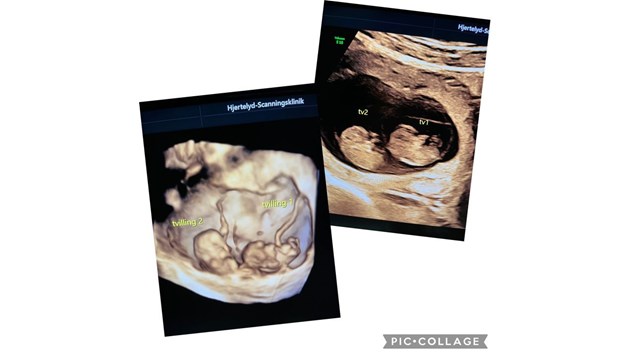

2 små enæggede tvillinger

Billeder er taget i uge 8+5 i både 2D og 3D

Fostrene er 31 og 33 mm.